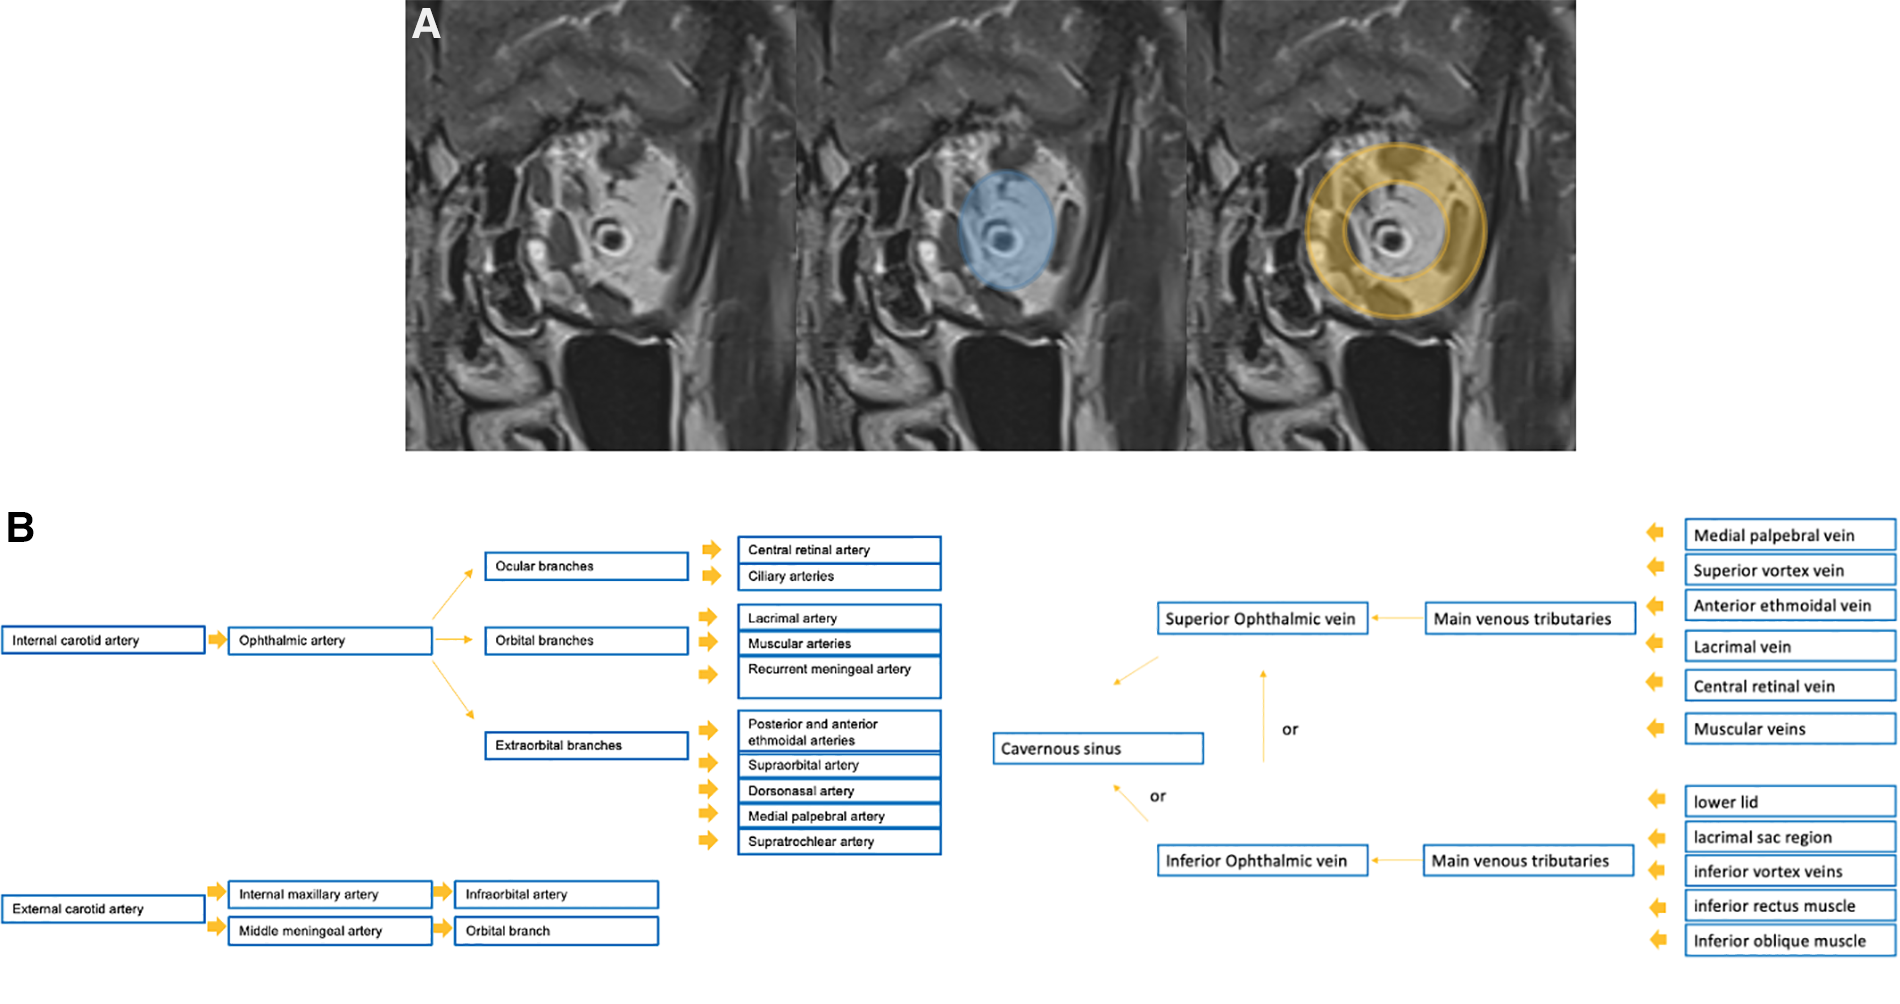

Imaging evaluation represents an important clue within the diagnostic management of vascular anomalies, and cannot overlook orbital anatomy. For this reason, detailed schemes of the orbital spaces and of the vascular supply of the orbit is provided in Figure 1.

Figure 1. Detailed schemes of the anatomical spaces of the orbit on the coronal T2w sequence (A: the intra-conal space is depicted in blue, while the extra-conal in orange) and of the vascular supply of the orbit (B).